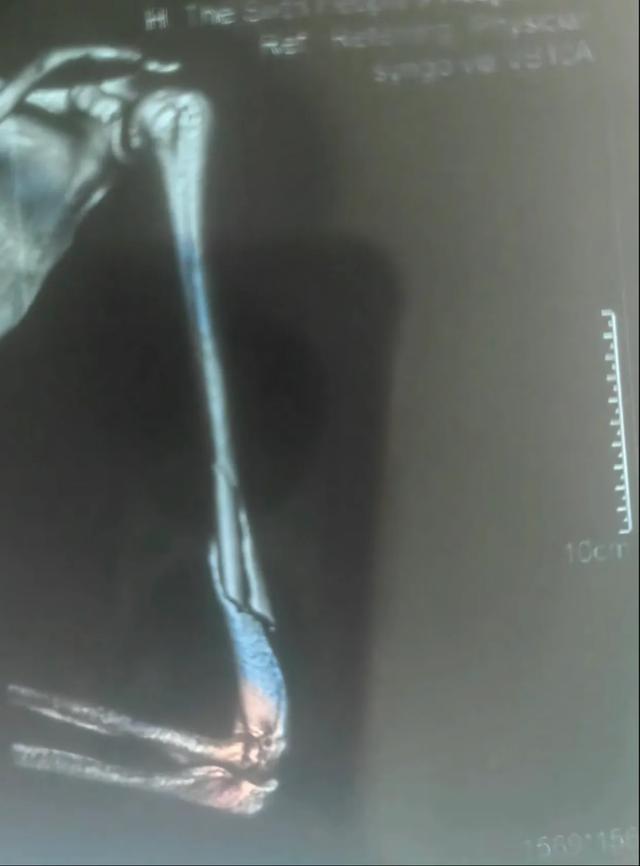

家长火速将孩子送往上海市儿童医院急诊,经急诊X光检查确诊为"右肱骨干粉碎性骨折"。

肱骨是上臂最粗壮的骨头,此类骨折通常伴随剧烈的疼痛和明显的畸形,还容易造成桡神经损伤,该神经一旦损伤,会造成永久性的功能障碍,包括无法抬手腕和翘拇指。

为最大程度减少手术创伤、避免损伤生长板、留下微小疤痕,骨科团队决定为其实施微创弹性髓内钉(TEN)固定术。与传统的大切口手术相比,这种技术仅需在骨折远端开两个微小切口,将具有良好弹性的钛合金髓内钉插入骨髓腔,像“支架”一样从内部将骨折断端对齐、固定。手术时间短、出血少、恢复快。